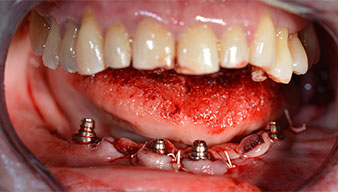

Les piliers angulés (35°) ont été vissés pour compenser la divergence des implants distaux. Ainsi, le profil

d'émergence de tous les implants doit être le plus perpendiculaire possible par rapport au plan occlusal. Il s'agit

d'une condition préalable à la pose en occlusion de la prothèse provisoire puis permanente (Fig. 15 et 16).

Implants

Fig. 15

Fig. 16